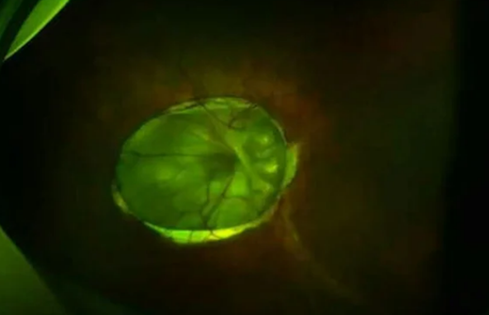

Lạ lùng người phụ nữ 'mọc hoa' trong mắt suýt bị mù, bác sĩ phát hiện điều đáng sợ

Hình ảnh chụp con mắt với những đường vân trông như một bông hoa bìm bìm. Chỉ đến năm 38 tuổi người phụ nữ mới biết mình mắc bệnh hiếm gặp.